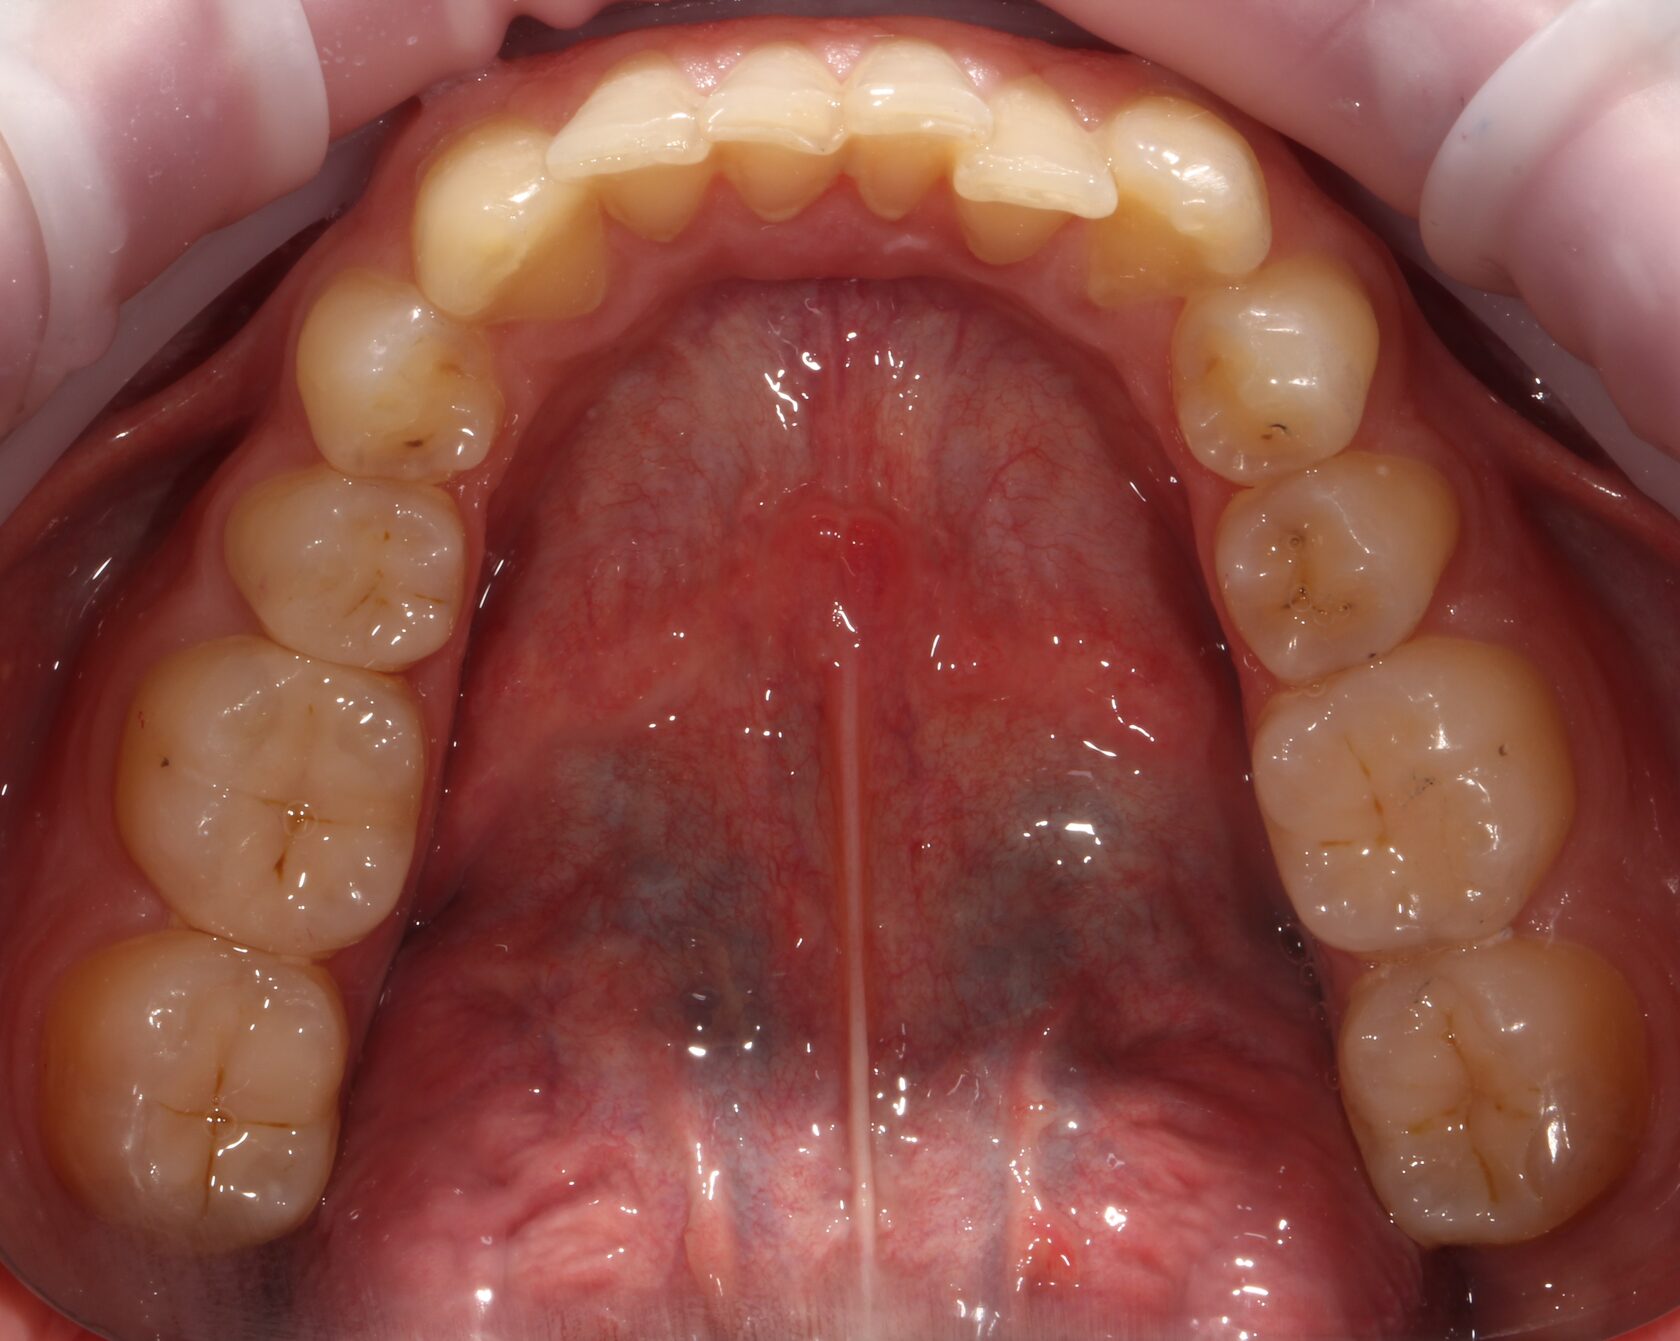

Результат комплексного лечения пациента командой врачей нашей клиники.

Выполнено:

1 Комплексная диагностика и планирование лечения.

2 Лечение всех зубов пораженных кариозным процессом и замена всех несостоятельных пломб.

3 Удаление зубов мудрости.

4 Установка дентальных имплантатов в зоны удаленных зубов.

5 Финальное рациональное протезирование с опорой на дентальные имплантаты.

6 Динамическое наблюдение с 2022 года.